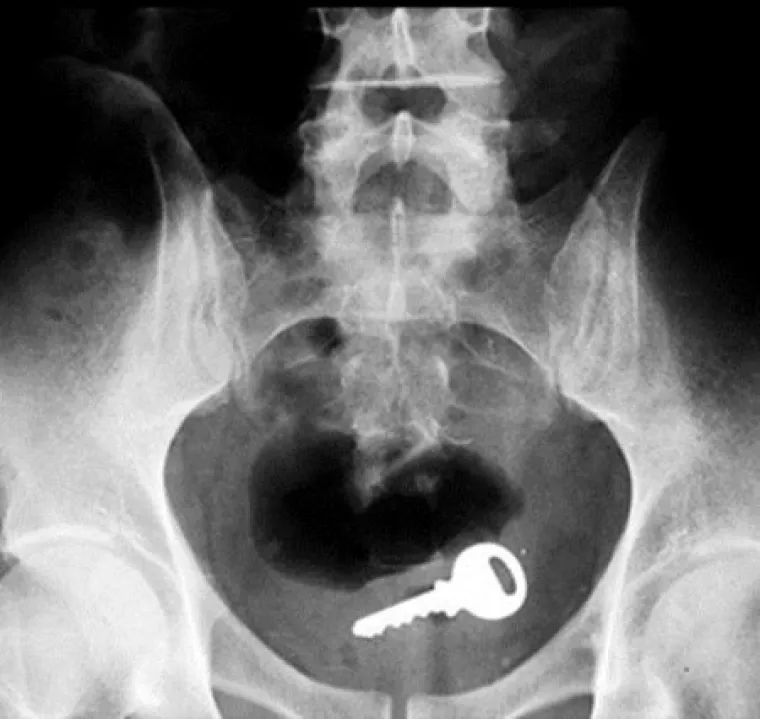

Doktori podijelili povjerljive slike pacijenata koji su u sebe ugurali sve i svašta

Ključ